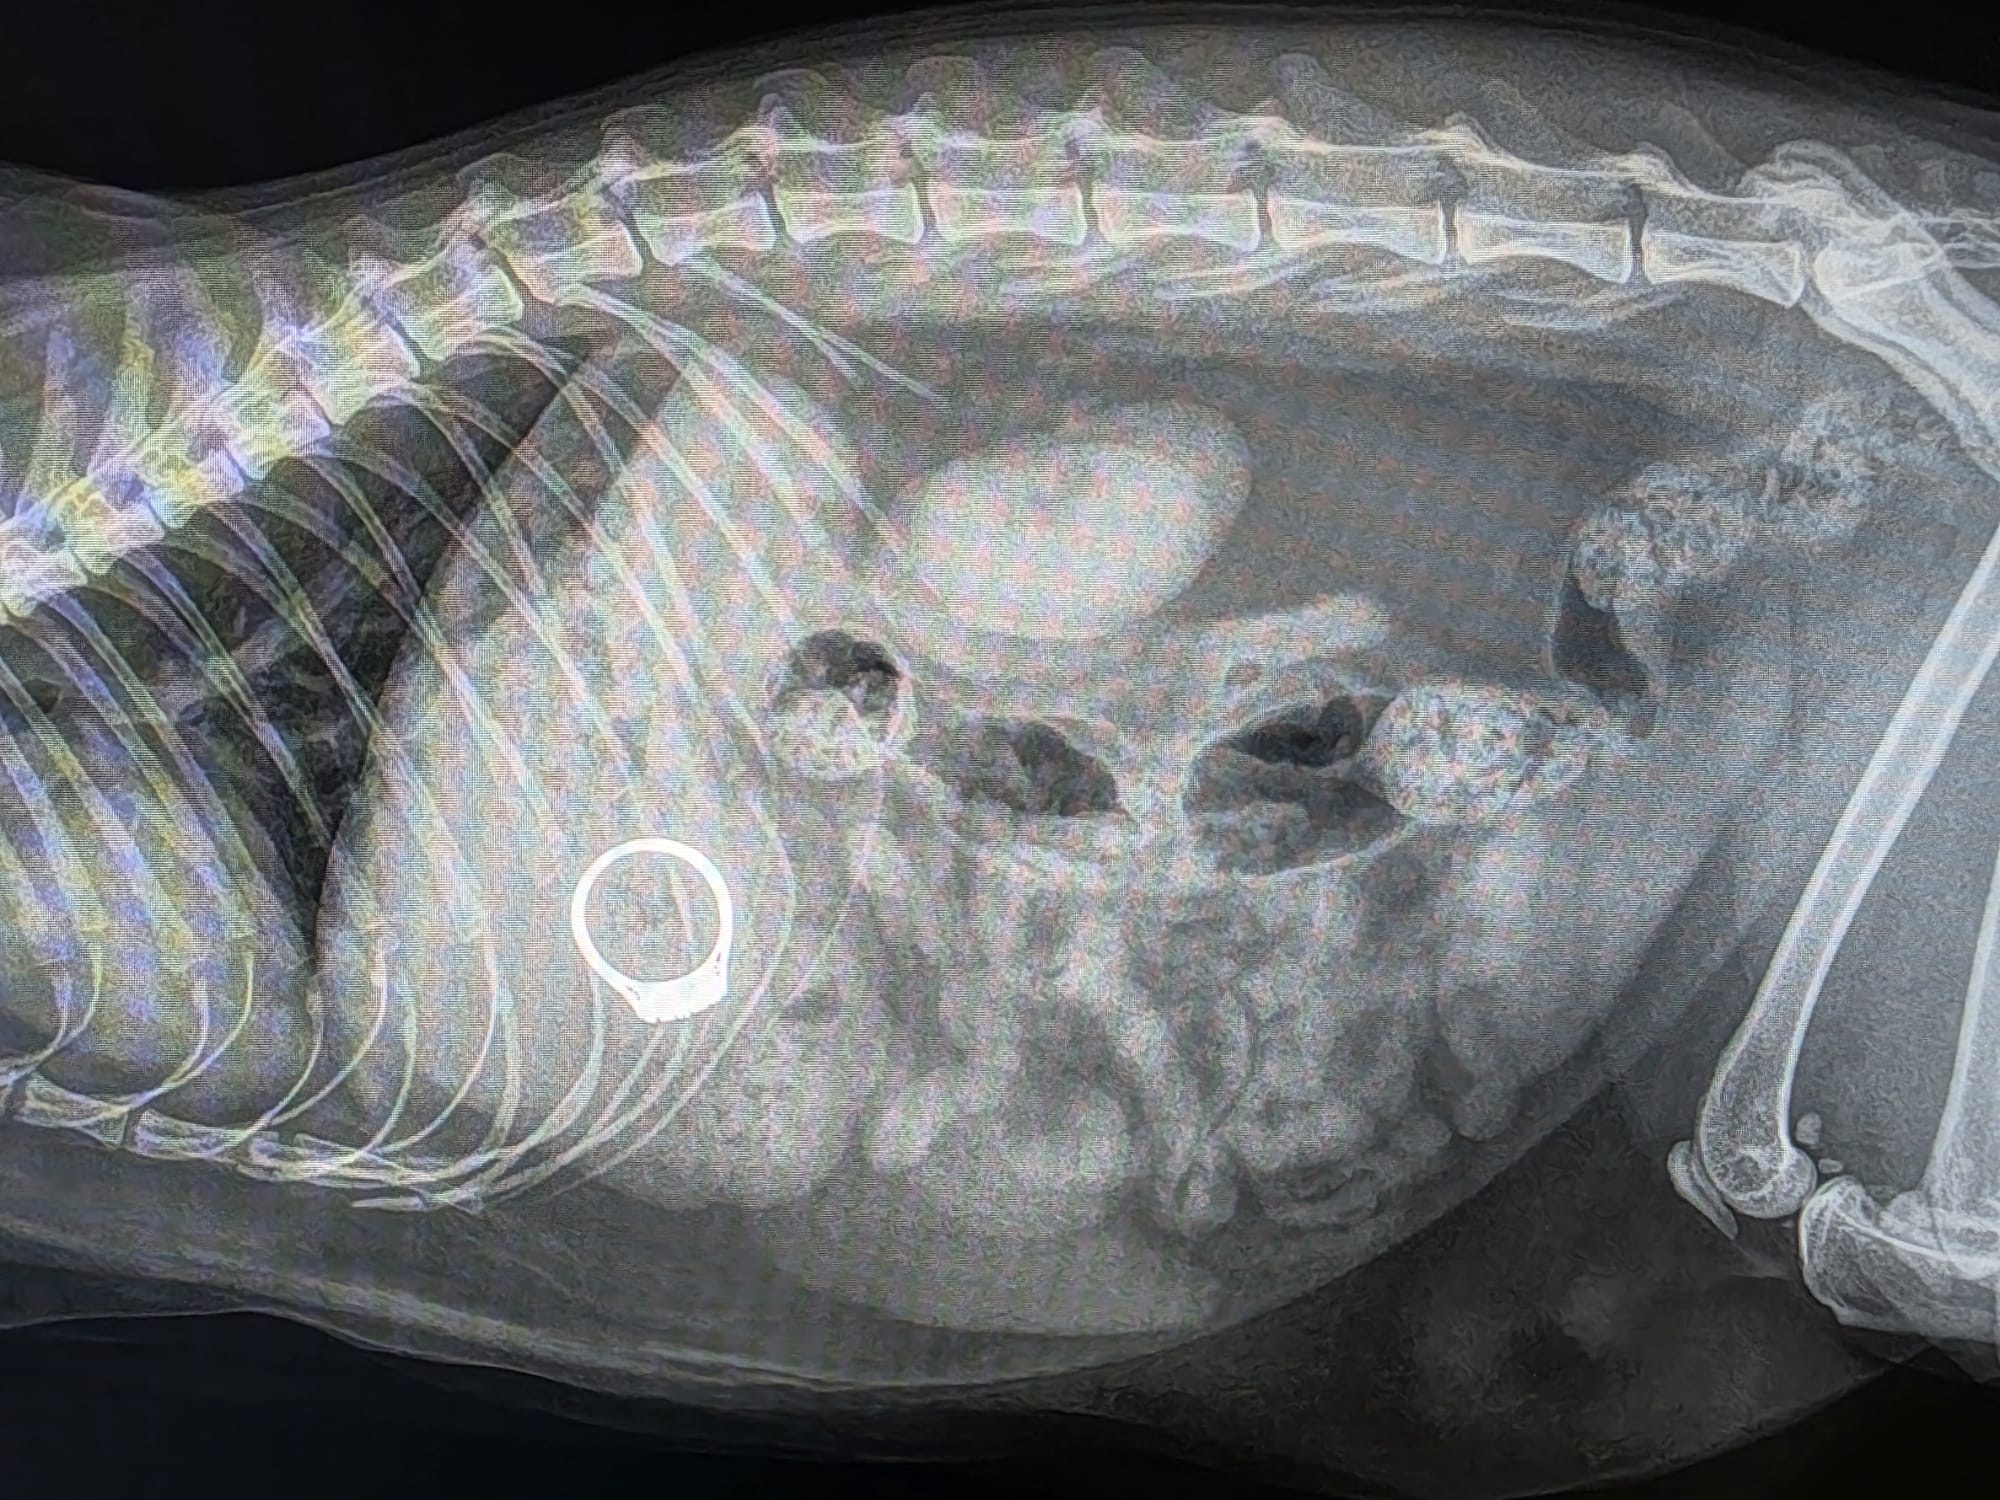

Once Su arrived, our team performed radiography to determine exactly where the ring was located. The X-ray clearly showed the ring sitting in Su’s stomach (see image below), confirming that it had been swallowed whole.

Radiograph showing the ring in Su’s stomach!